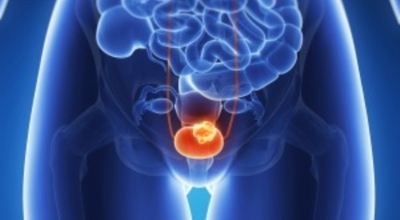

사실 방광암은 주변에서 흔하게 듣는 암 종류는 아닌데요, 방광에도 암이 일어날 수 있다는 사실이 놀랍네요. 방광암은 방광내에 소변이 닿는 점막에 나타나는 암으로 초기에는 증상이나 통증이 눈에 띄게 나타나지는 않지만 초기 몇 가지 증상들로 의심하고 조기에 관찰되는 경우가 많다고 합니다. 오늘은 방광암 초기증상에 관하여 알려드리겠습니다.

방광암이란

방광암은 여성보다 남성에게 발생할 확률이 상대적으로 높은 대표적 3대 비뇨기암으로 유명하고, 비뇨기계 암 중 발병률이 높아 남성암 중에선 7위라는 타이틀을 차지하고 있어요. 2017년 기준으로 보면 국내에서는 약 4400명이 방광암으로 진단받았으며 그중에서도 약 80프로가 고령 환자였다고 합니다.